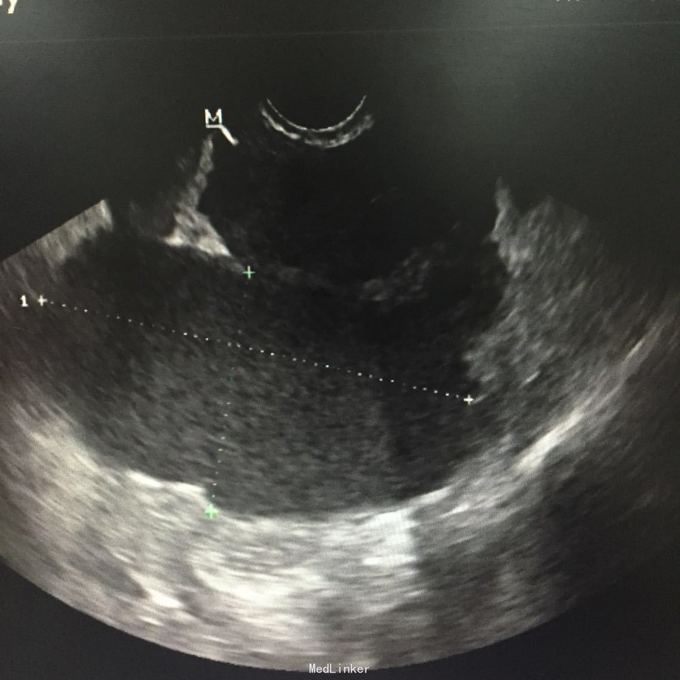

查体:右侧附件区可及一10*5cm包块,囊性,无压痛、反跳痛,左侧附件区可扪及5*5cm包块,囊性,轻压痛,无反跳痛。辅助检查:彩超:筛查附件区囊性包块,考虑内膜异位囊肿可能性大,左侧一个,大小58*49mm,右侧多个融合,范围91*48mm。

诊断:双侧卵巢巧克力囊肿。入院行剖腹探查术,术中见,大网膜、肠管、膀胱反折除及子宫前后壁可见附着褐色陈旧粘稠血块,大网膜与子宫底部及右侧前壁粘连,左侧卵巢增大约6*5*5cm,右侧卵巢增大约10*6*6cm,予以行腹式双侧卵巢囊肿剔除术+盆腔粘连松解术。术后病理:双侧卵巢巧克力囊肿。